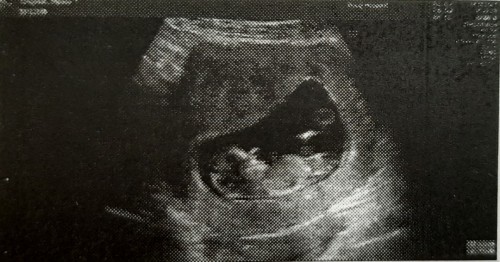

ซาวตอน 11w 2d ค่ะ ตอนนี้ 15w 2d